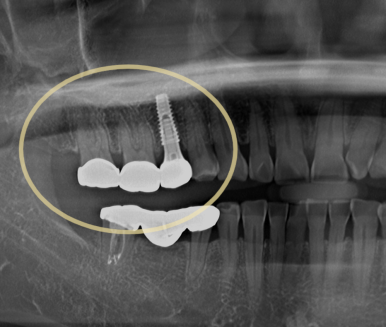

“오래 쓸 수 있고 확실한 치료”를 원하셔서 즉시 임플란트를 진행했습니다.

| 임플란트 식립 후 | 임플란트 식립 후 최종보철까지 완성 |

👉 같은 날 파절 치아 발치 + 임플란트 식립

👉 인접 어금니는 크라운 수복으로 회복

👉 치료 후 매우 만족하셨습니다 😊